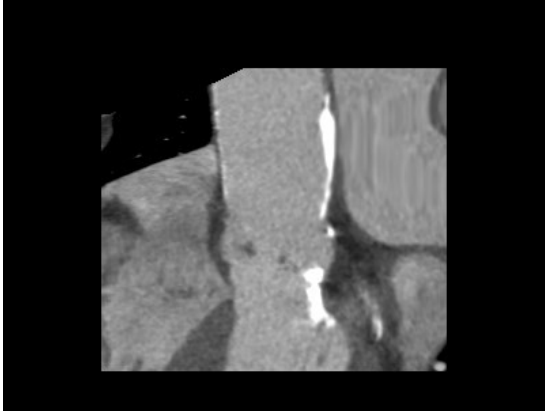

二难:血管严重病变

合并有严重的冠状动脉疾病、左锁骨下动脉严重钙化性狭窄、主动脉及分支严重钙化(也称为“瓷化”),搭桥手术风险也很高。

左主干钙化病变,主动脉严重钙化(也称为“瓷化”),外科搭桥风险高;左锁骨下动脉严重钙化性狭窄,如果不预先处理,后续外科手术时可能会影响脑循环......